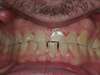

Nous avons reçu notre patient qui souffre de bruxisme intense et s'est errodé 3/4 mn de son étage inférieur.

Nous avons surélevé son occlusion par des onlays postérieurs pour dégager de l'espace antérieur et 6 couronnes antérieures ont été posées. Nous en avons éclairci la teinte globale des dents